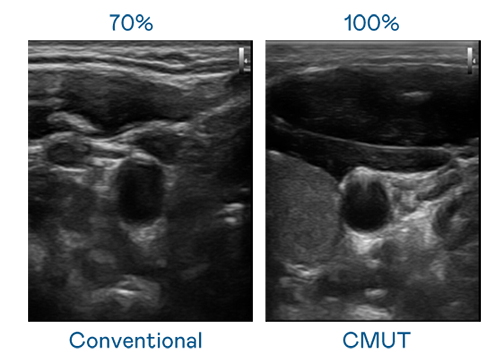

CMUT 技术是一种用电容式微机电元件来产生超音波讯号的技术。与传统 PZT 压电式技术相比,CMUT 频宽增加 30%,更宽频的超音波讯号让影像解析度大幅提升,是实现高影像品质医疗超音波扫描、促进精准医疗发展的关键技术。

大频宽带来超清晰影像

超音波影像的解析度高低,首先取决于探头能发出的讯号频宽。yd12399云顶集团 CMUT 可提供高清晰的超音波讯号,提供高频宽、高灵敏度、影像纹理细节更高的超音波影像,协助医护人员缩短影像判读时间及利用精准的医疗影像进行诊断。